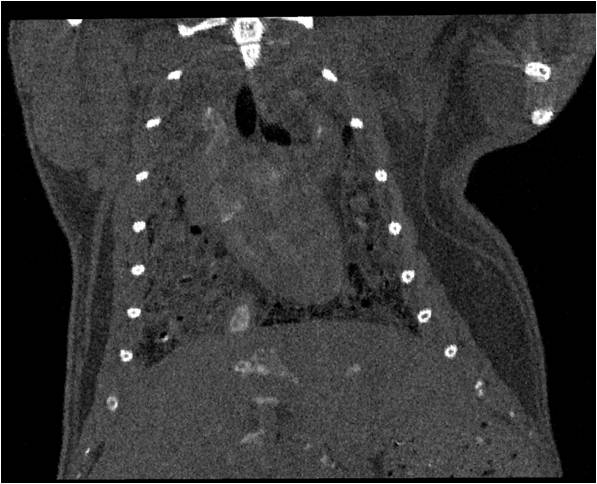

腫瘤血管生成

肺轉移

小鼠模式,22.5μm像素

正常

8天 14天

無造影劑注入 造影劑注入